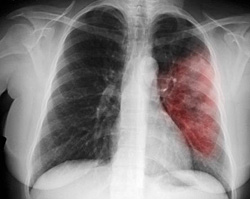

Локализация процесса вдоль корня легкого затрудняет рентгенологическую диагностику заболевания. Рентген в прямой проекции показывает расширение корня легкого, увеличение тени средостения, но дать более точные характеристики не представляется возможным. Более детальную информацию может дать компьютерная томография. Однако даже при качественном изображении остаются иногда вопросы.

Основным методом диагностики прикорневой пневмонии являются рентгенологические методы исследования. На рентгенограммах врач может увидеть локализацию воспаления, дифференцировать прикорневое воспаление лёгких от других заболеваний дыхательных путей. Но при прикорневой пневмонии интерпретация рентгенографического исследования может быть затруднительной. Затемнение от воспалённого очага часто наслаивается на корень лёгкого. В результате легочный корень на рентгеновском снимке «расширяется», что может указывать на новообразование или туберкулёз.

Наиболее точным методом диагностики прикорневой пневмонии является компьютерная томография. Она позволяет более точно определить состояние бронхов и легочной ткани, лимфатических узлов, увидеть неоднородную структуру тени. Для того чтобы определить возбудитель и его чувствительность к антибактериальным препаратам, проводят исследование мокроты.